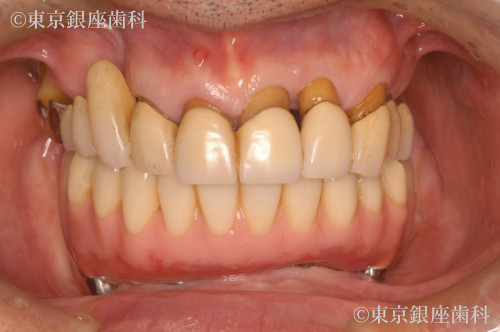

難しい神経位置の症例で回復まで半年以上を要した60歳代男性のインプラント症例

下顎の神経露出に近い難症例。術後一時的に神経麻痺が出たが、理学療法と投薬で半年以上かけて回復。信頼関係の中で上顎治療も希望され、現在は上下とも安定。

上下ワンデイインプラント(サイナスリフト併用)